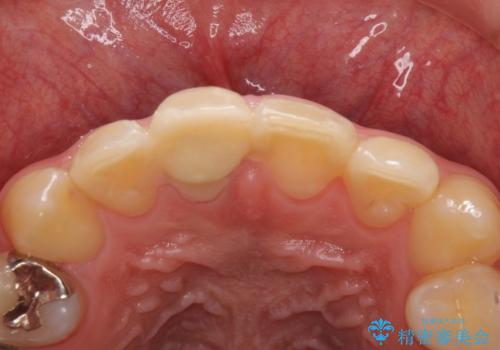

- 治療中の前歯と口腔内にある銀歯が気になるとのことで来院された患者様です。

土台に含まれている金属も含め、口腔内の金属は全て除去し、根管治療が必要な歯は根管治療を行い、オールセラミッククラウンやセラミックインレーにて治療することとしました。

途中来院されない時期があったため、初診から終了まで期間がかかりましたが、根管治療を行った歯の根尖病変はいずれも改善を確認することができました。

口腔内の金属が全てなくなり、患者様には大変満足していただきました。